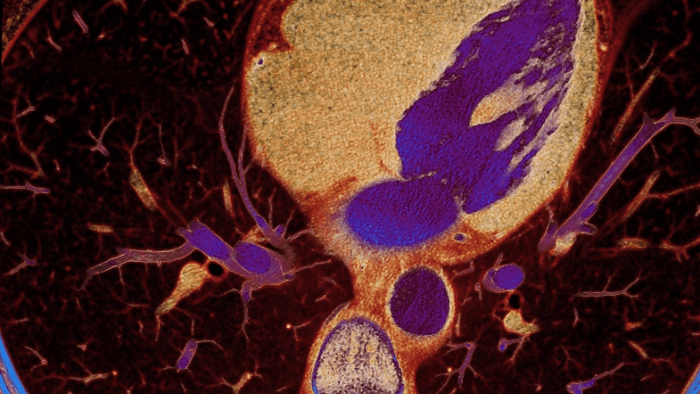

Spectral detector simultaneously absorbs and differentiates high and low energy from a single polyenergetic X-ray beam. Spectral results are acquired within a single scan without the need for special modes.

Detector-based spectral CT simultaneously absorbs high and low energies in the same time and space.